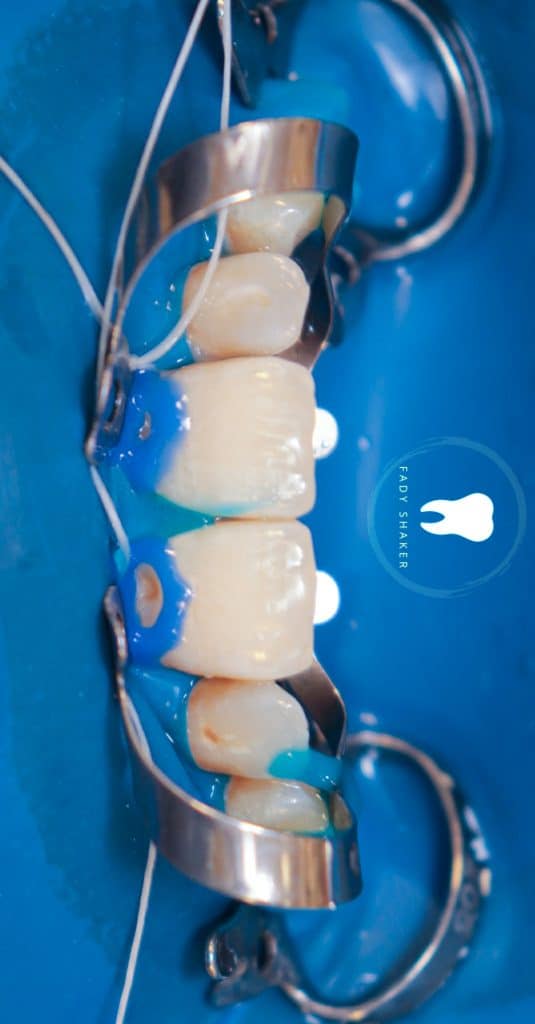

2-apply rubberdam and secure it by clambs on #14 & #24

then i did inversion for the sheet& secure it with floss ligature

3-remove carious lesion& initial excavation

7-selective acid etching for 25S

8- apply all bond universal two layers without curing between them

9- solvent evaporation by new bond brush and avoid using air thinning for long time to not increase oxygen inhibited layer

10-apply 0,5mm highly filled flowable composite then light cure